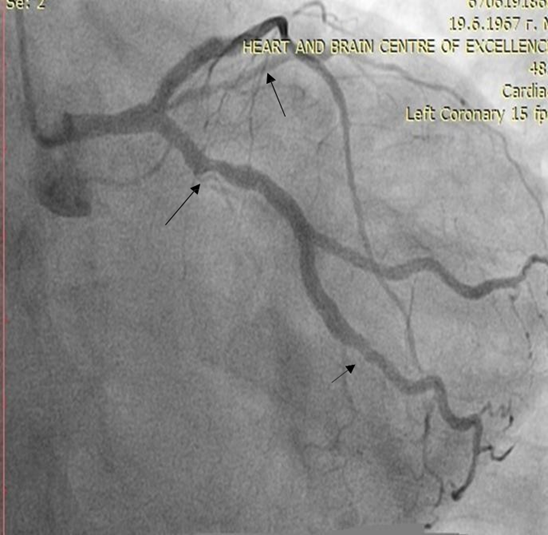

Use of imaging methods for early identification of cardiovascular disease such as 12-lead electrocardiogram, echocardiography, computed tomography angiography scan, selective coronary angiography with intravascular ultrasound (IVUS) and Fractional Flow Reserve (FFR) would also benefit and support the diagnosis (figure 3).

Figure 4: Selective coronary angiography of a 55-year-old woman with established ischemic heart disease, LDL 4 mmol/l, total cholesterol 6 mmol/l, on therapy with rosuvastatin 20 mg/per day. and ezetemibe 10 mg/per day, in which we started treatment with a PCSK9 inhibitor.